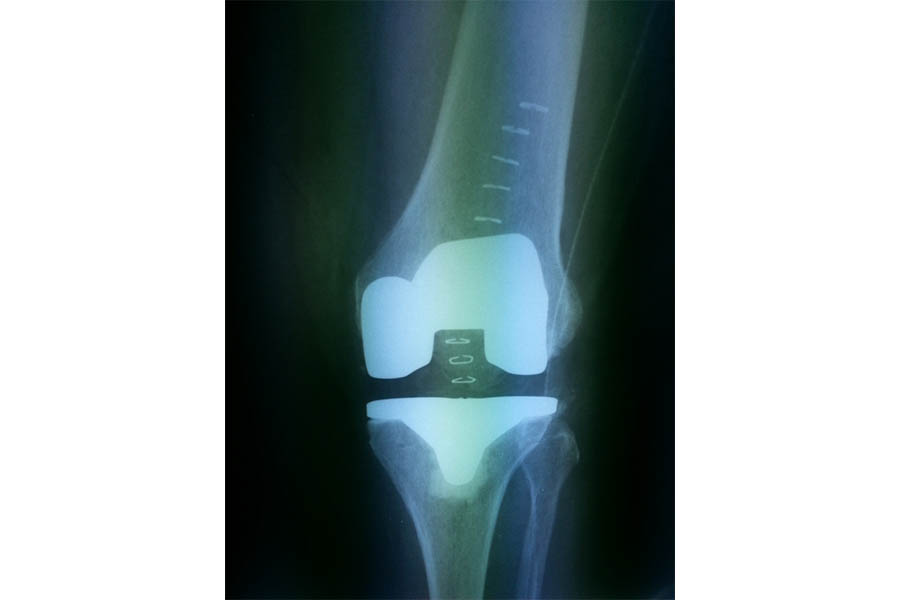

Total Knee Replacement

Case 1